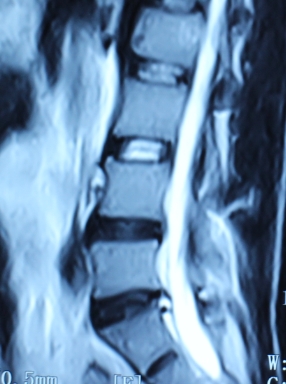

1.患者邹某,男,79岁,因“腰痛双下肢疼痛1年余,加重并间歇性跛行2月”于2014年3月26日入院。入院见患者腰痛病双下肢疼痛、麻木,间歇性跛行,行走约10余米,休息后略缓解。查:直腿抬高试验左40°(+),右55°(+),加强试验(+),腰背伸试验阳性。双侧膝腱未引出,跟腱反射减弱,双侧踇背伸肌力Ⅳ级。入院后诊断为腰椎管狭窄症。患者既往患糖尿病、高血压、冠心病病史。入院后完善检查,明确诊断,请相关科室会诊后认为手术风险极大。经科室讨论后行经皮椎间孔镜下髓核摘除并椎管扩大成形术,手术麻醉方式为局麻。于2014年3月29日行手术治疗,经椎间孔入路椎间孔镜下髓核摘除椎管扩大成形术。手术顺利,术中无出血,手术时间约40min。术中可与患者交流。术后患者即可感双下肢无疼痛,第二天佩戴腰围下地活动后双下肢无不适。术后半年复查腰椎MRI示突出髓核已摘除,神经根无受压。术后随访1年,患者目前病情恢复良好,无下肢疼痛、麻木,无间歇性跛行。

术后半年MRI